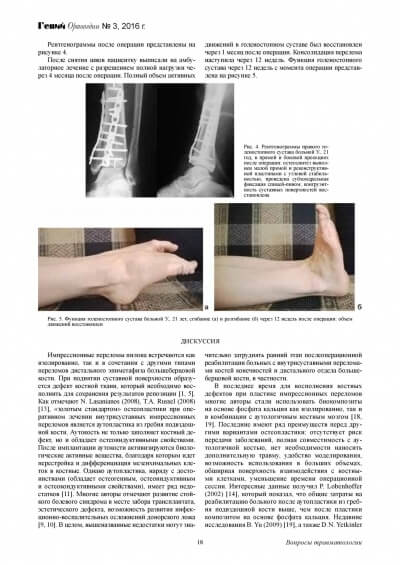

Замещение дефектов костной ткани у животных

Эндопротезы тазобедреного сустава